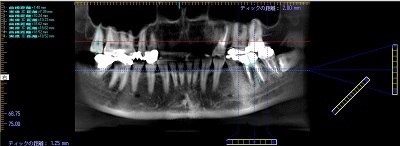

レントゲン撮影・CT撮影・口腔内Scan ・シュミレーションソフトによるプランニング

インプラント予定部位の骨の状態、周囲組織の状態を診査します。CTを用いることで多角的に診断することができます。当院では最新の歯科用コーンビームCTを設置し、低被爆を実現しています。

当院では最新のドイツKavo 社製のCTを設置しています。

低被爆で細かな診断と埋入シュミレーションを行い診断をしております。

シュミレートした画像をお示ししながら検査結果と治療計画をご提案し、ご質問にお答えします。